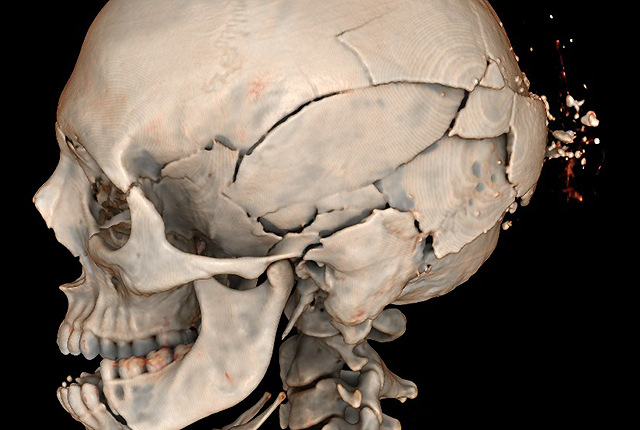

Cause of death? CT scans shed new light in forensic probes

Q&A: King County’s medical examiner and a UW Medicine radiologist discuss a program that hints at change in U.S. death investigations.